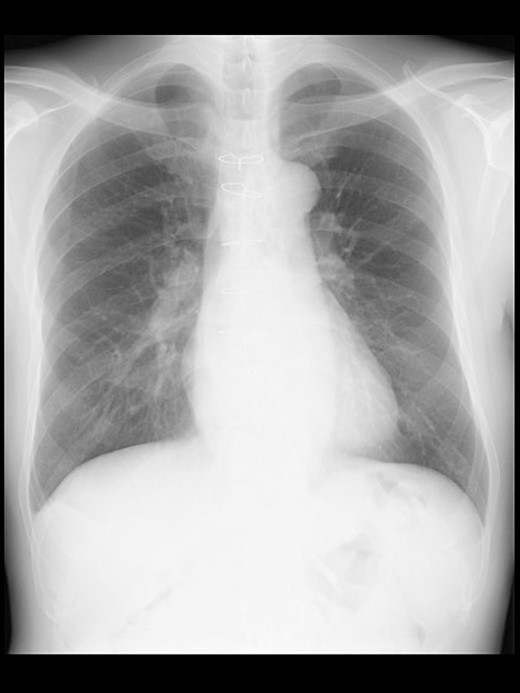

Even though the patient did not receive supplemental oxygen in the ward, SpO2 remained at 98%. Chest radiographs were not taken on the day of surgery. However, a chest radiograph taken in the upright position on postoperative Day (POD) 1 revealed a pneumothorax on the right side (Fig. 2), although he had no respiratory symptoms. Radiographs on PODs 2 and 3 revealed the pneumothorax remaining unchanged (Fig. 3). The patient was discharged from the hospital on POD 3 without any respiratory symptoms. A chest radiograph taken on POD 19 showed no remaining pneumothorax.

A chest radiograph in the upright position on POD 1 showing a right pneumothorax (arrowheads).